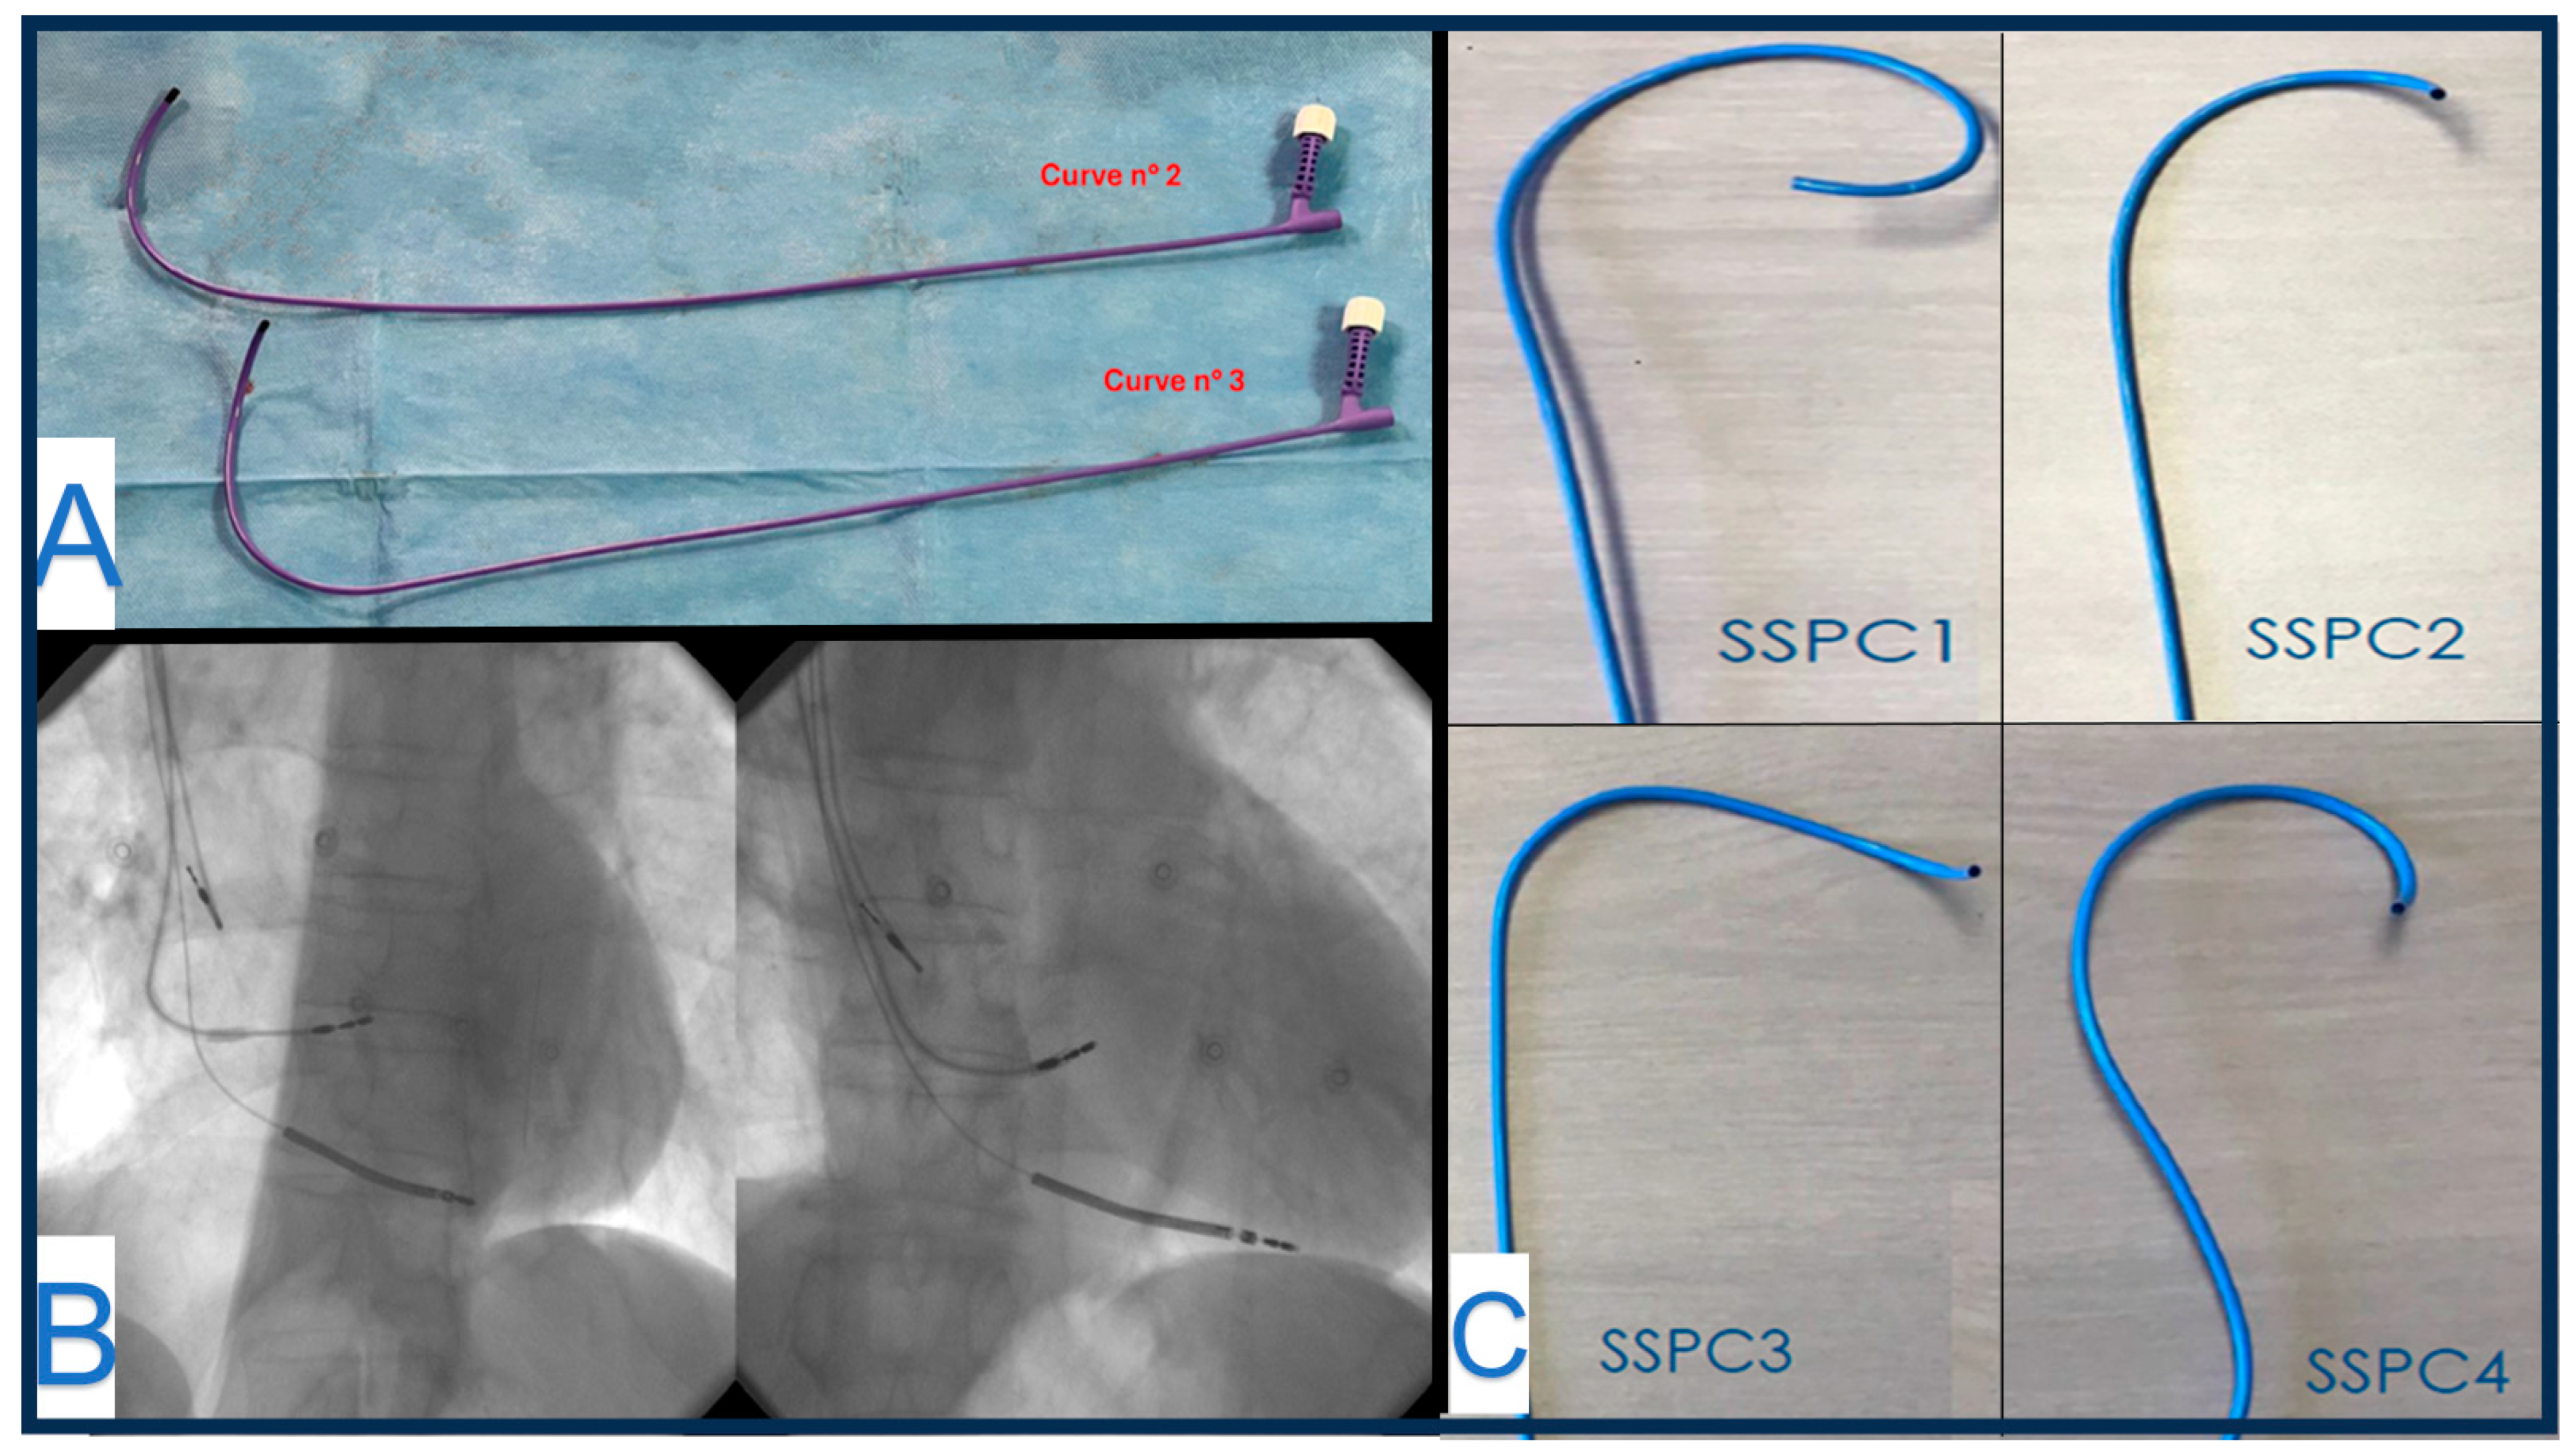

4. Stylet-Driven Leads

- Zanon, F.; Marcantoni, L.; Pastore, G.; Baracca, E. Left bundle branch pacing by standard stylet-driven lead: Preliminary experience of two case reports. Heart Rhythm Case Rep. 2020, 6, 614–617. [Google Scholar] [CrossRef] [PubMed] [PubMed Central]

- De Pooter, J.; Wauters, A.; Van Heuverswyn, F.; Le Polain de Waroux, J.B. A Guide to Left Bundle Branch Area Pacing Using Stylet-Driven Pacing Leads. Front. Cardiovasc. Med. 2022, 9, 844152. [Google Scholar] [CrossRef] [PubMed] [PubMed Central]

- Özpak, E.; Van Heuverswyn, F.; Timmermans, F.; De Pooter, J. Lead performance of stylet-driven leads in left bundle branch area pacing: Results from a large single-center cohort and insights from in-vitro bench testing. Heart Rhythm 2024, 21, 865–873. [Google Scholar] [CrossRef] [PubMed]